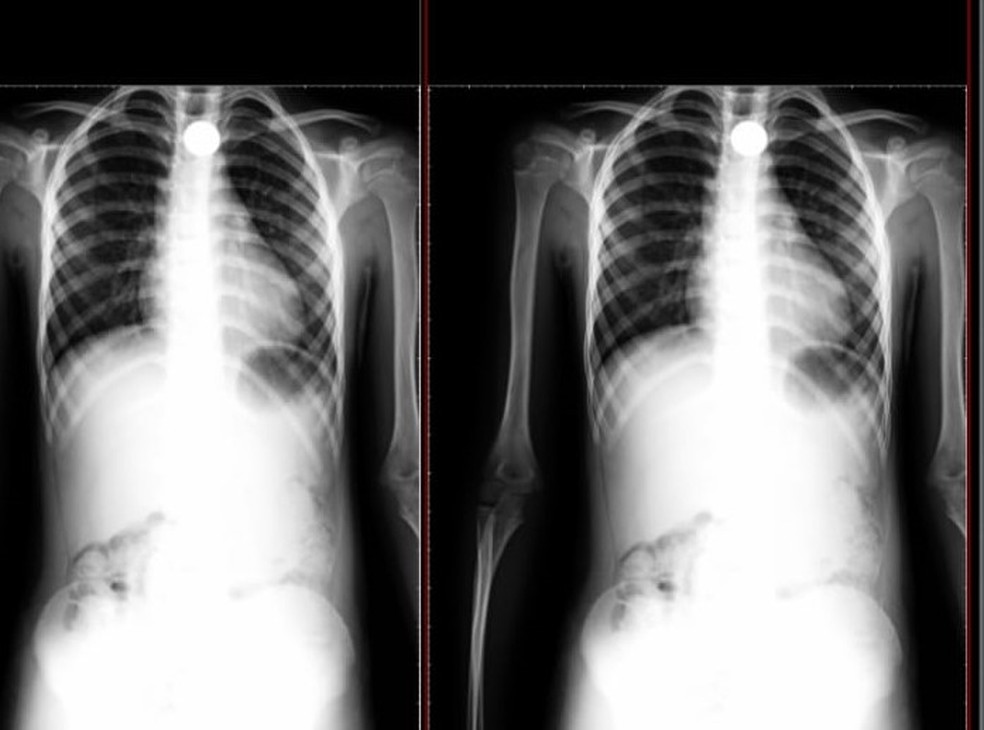

Segundo o G1, o menino de 8 anos chegou perto do pai e contou que havia engolido a moeda, e já mostrou sinais de falta de ar, o que preocupou a família, que levou a criança com urgência para um hospital, onde foi confirmado através de um raio-x, a existência do material.

A vítima está com dor no peito, sem se alimentar e ainda espera transferência para outro hospital, onde se possa fazer cirurgia.